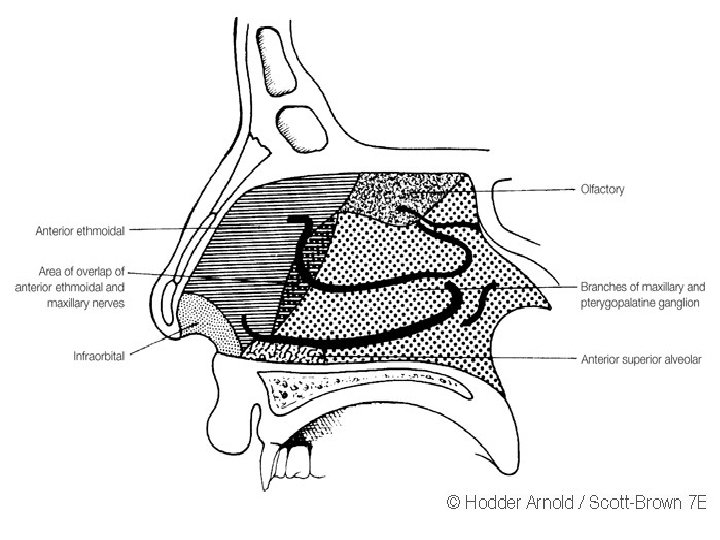

• Trigeminal nerve carries the common sensation via ophthalmic and maxillary divisions. • Special sensory (smell) carried via olfactory nerves.